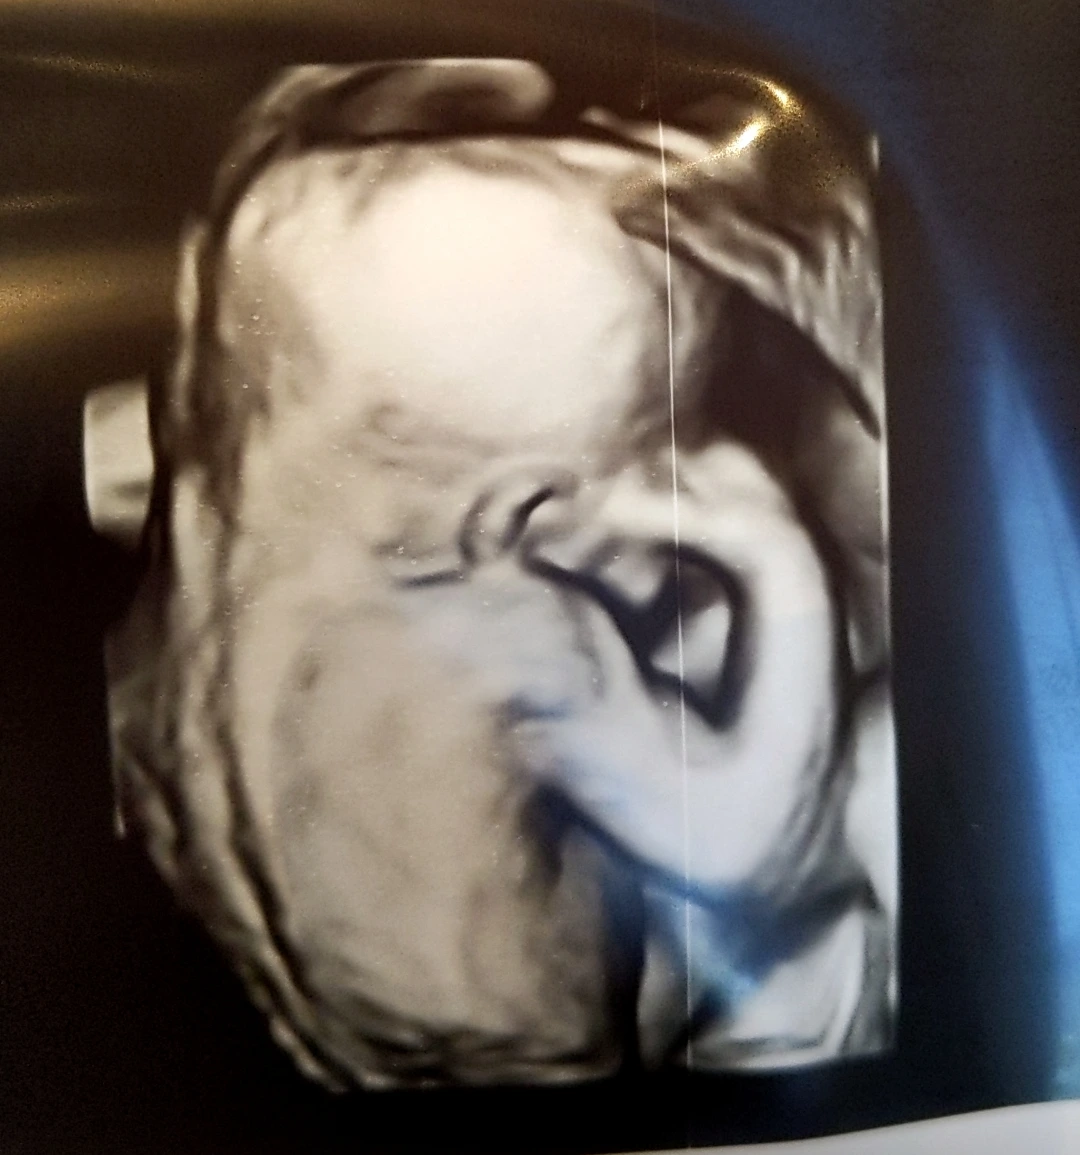

#7 お姫様(공주님)

何もついてないので女の子だと思います

(아무것도 안 붙어 있으니

여자 아이일 거예요)

임신 21주 차에 아기의 성별을 알게 되었다. 여자 아기라니...♡ 미신이긴 하지만 배도 둥글기보다는 약간 뾰족하게 불렀었고 고기가 임신 전보다 더 맛있게 느껴져서 남자 아기인 줄 알았다.

여자 아기는 남자 아기와 다르게 생식기가 눈으로 확실히 확인되는 것이 아니고, 생식기가 탯줄이나 다리 등으로 가려진 걸 수도 있기 때문에 "여자 아기예요!"라고 단언하지 않고 "여자 아기일 거예요"라고 말하는 것 같다. 물론 확실히 여자 아기인 걸 알 수 있는 표시도 있지만 우리 아기의 경우는 그게 잘 안 보이는 모양인지 임신 9개월 차인 지금도 가끔 물어보면 "- 일 거예요"라고 한다. 그래도 벌써 의사 선생님 5명 정도한테 물어봤으니 여자 아기인 게 확실하다고 믿고 있다.

비록 얼굴은 보여주지 않았지만 튼실한 뒷모습을 보여주며 엄마, 아빠를 안심시켜준 우리 공주님 사진으로 마무리♡